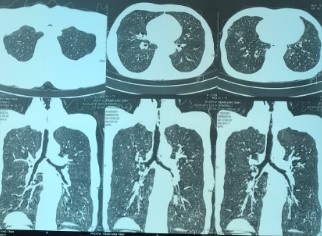

Bệnh nhân đã được chụp CT scanner ngực có hình ảnh hẹp khí quản, nội soi phế quản cấp cứu phát hiện thấy có tình trạng xơ sẹo gây chít hẹp gần hoàn toàn khẩu kính khí quản đoạn 1/3 trên, ngay dưới thanh môn. Tình trạng hẹp khí quản mức độ nặng có thể khiến người bệnh tử vong ngay lập tức.

| Hình ảnh hẹp khí quản của nam bệnh nhân. Ảnh: BSCC. |